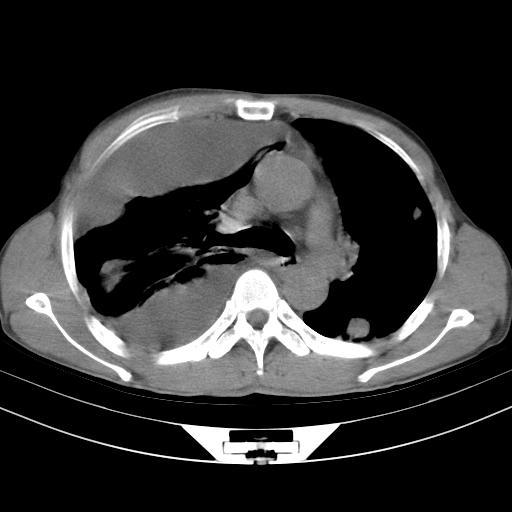

男性,44岁,结核病史多年。现胸闷气短,咳嗽,偶咳血。

右侧胸腔积液

右肺下叶不张

双肺多发结节影最分空洞形成考虑占位不除外结核

1、右侧大量胸腔积液伴右肺压缩性膨胀不全,建议抽液治疗后复查 2、两肺继发性tb伴空洞形成。

1)两肺继发性肺结核伴空洞形成,左肺多发性结核球。2)右侧大量胸腔积液伴右肺部分膨胀不全。3)纵隔淋巴结肿大。